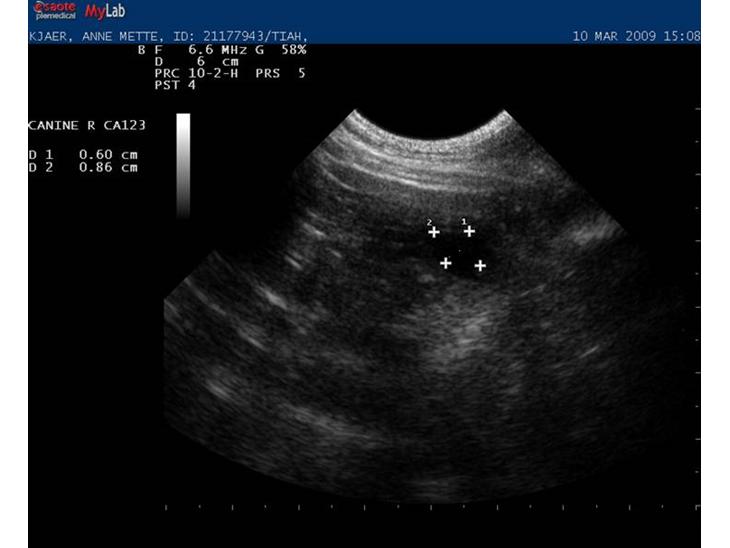

Tiahs scanningsbilleder fra idag af. Foerste scanning. Hun er 25. dagen fra foerste parring og 20. dagen for sidste. Fosterblaererne er stadig meget smaa kun omkring 1cm lange saa jeg tror jeg skal regne fra sidste parring for at faa det mest noejagtige resulat.